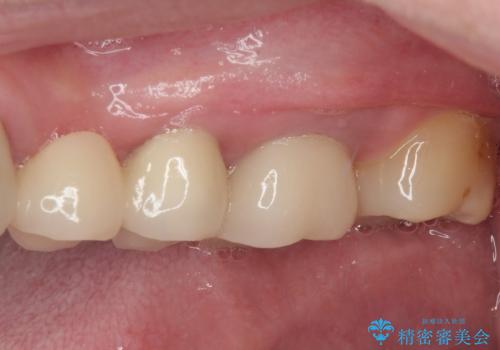

銀歯や欠損が大きいことから、虫歯治療後はオールセラミッククラウンによる補綴治療を行うこととしました。

やはりむし歯は大きく、一部歯髄を切除することとなりましたが、その後は良好な経過をたどっています。